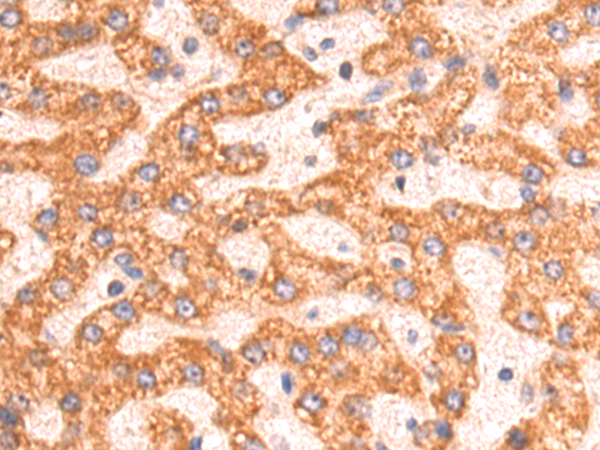

分类: 科研抗体货号: P08418别名: I; HSD3B; HSDB3; HSDB3A; SDR11E1; 3BETAHSD应用: WB,IHC反应种属: Human